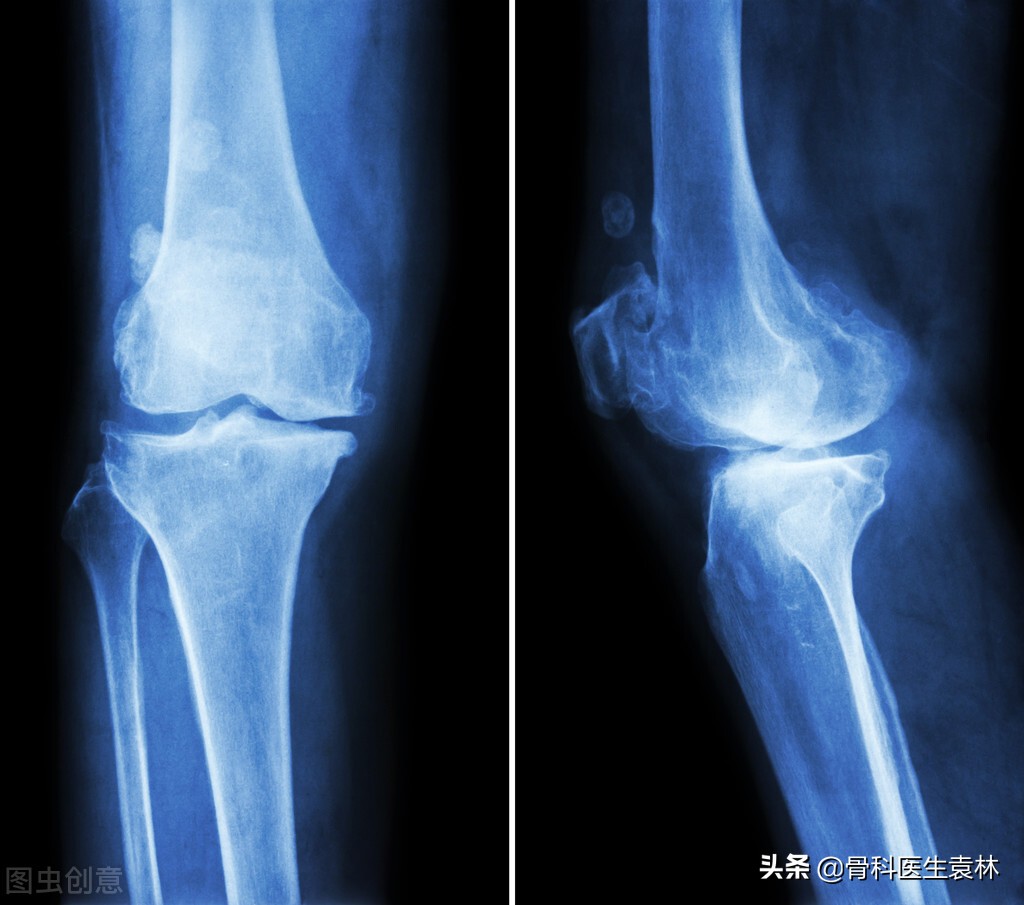

对骨刺不必恐惧。骨刺并非长入骨内的刺,在侧位X线片上是“刺”状,而在正位X线片上一般不显示。因为它有一种自身保护作用,以一般不会疼痛。有些患者出现疼痛,是因为有软组织(韧带、筋膜)损伤或劳损;有的是由于骨骼、软组织退行性病变产生导致疼痛的介质;有的是由于以上原因引起的骨内压增高。在休息时仍然疼痛(医学上称为休息痛),但不是刀割样锐性痛,而是沉闷、钝痛、酸困和说不出